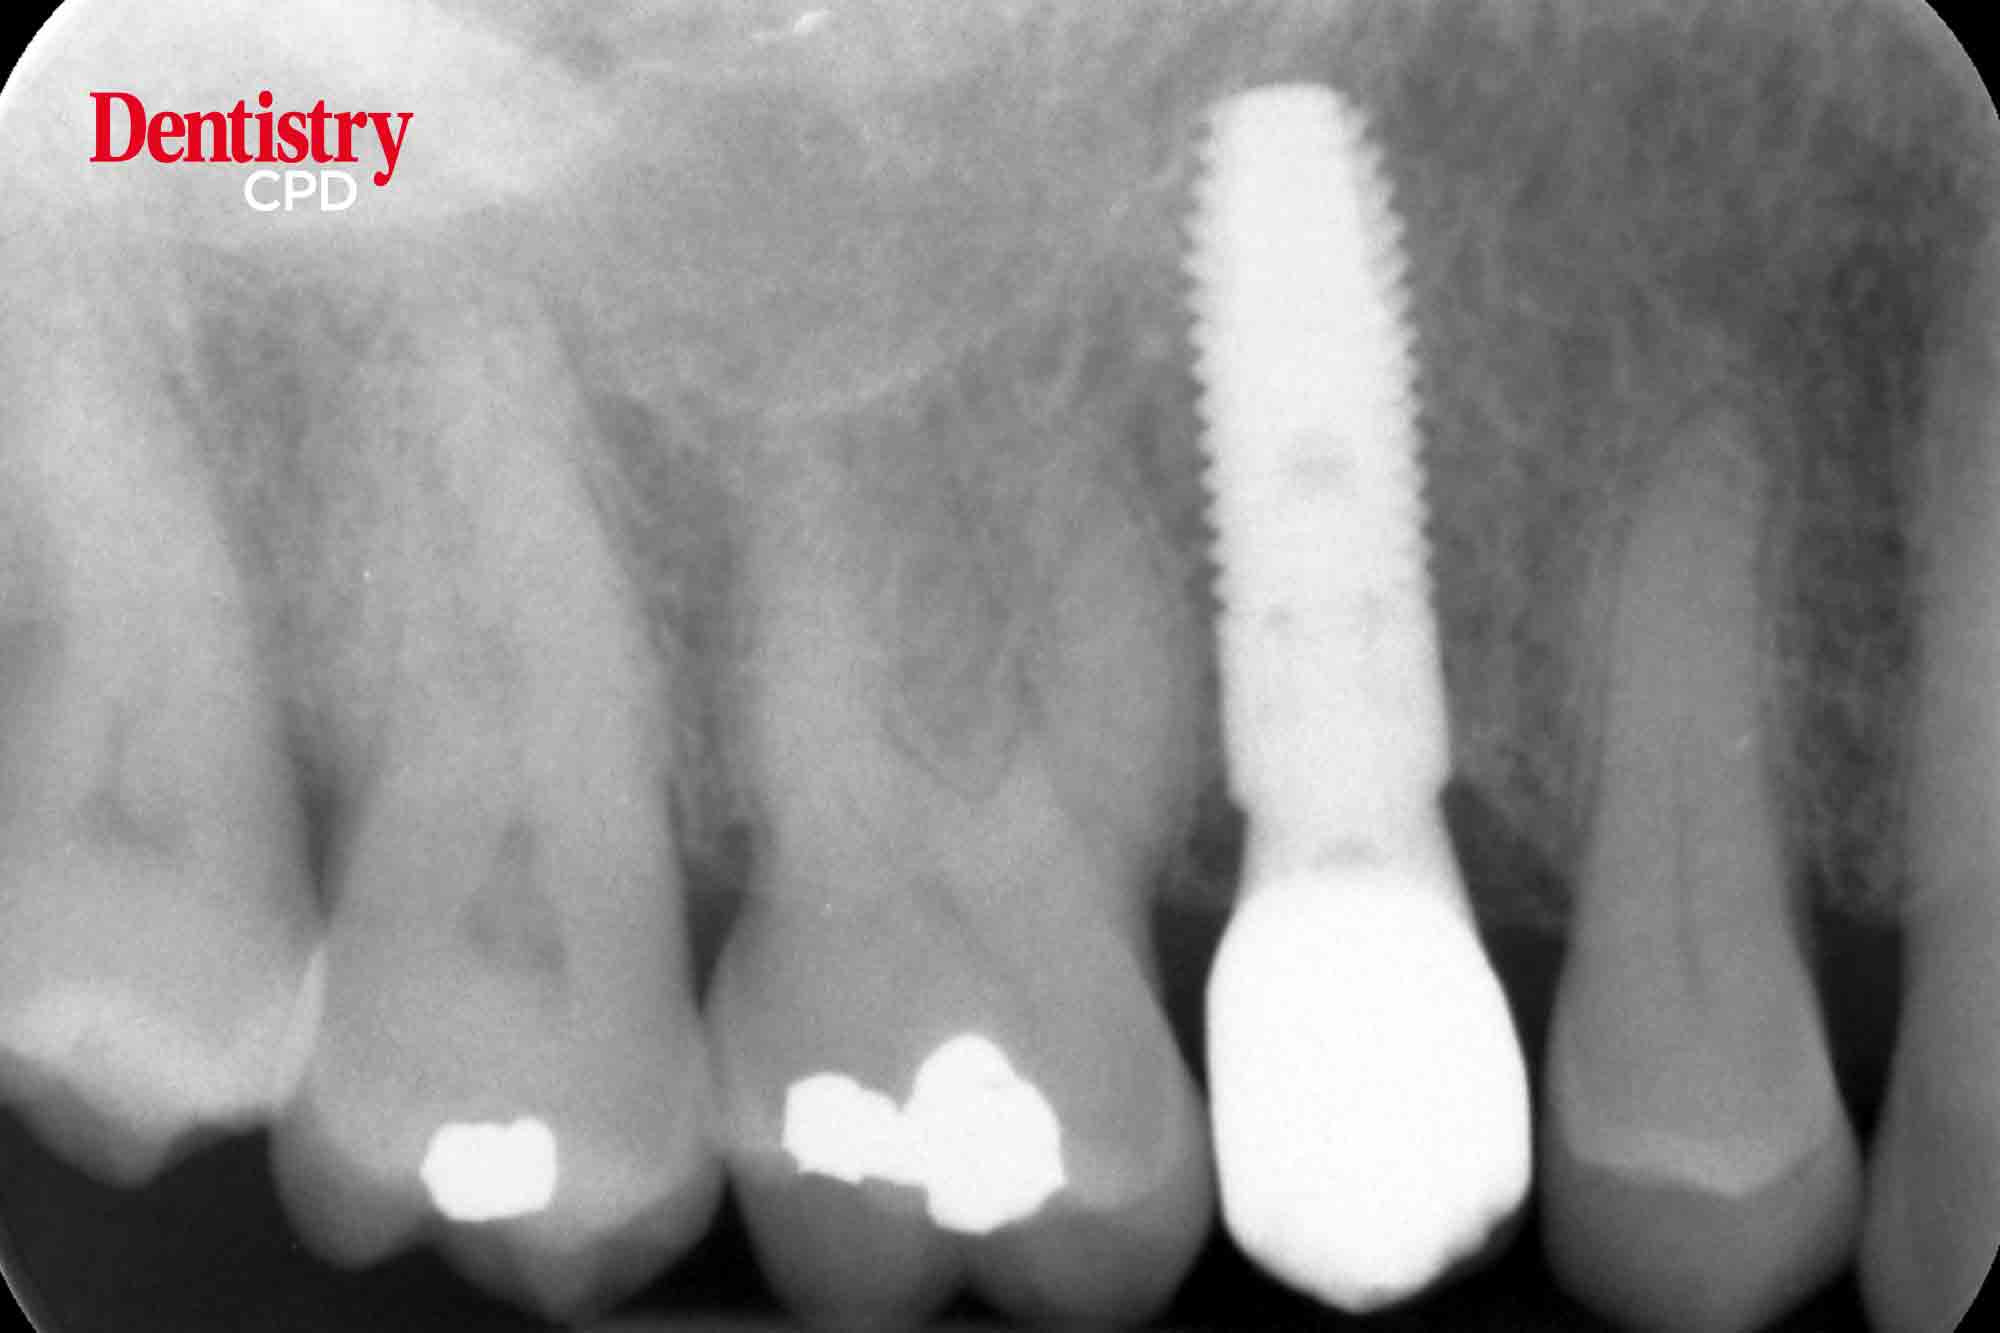

Michael Norton explores the new Primescan intraoral scanner for delivery of screw-retained, digitally designed implant-supported restorations.